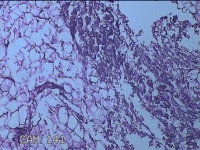

外阴部包块

性别

女

年龄

37岁

临床诊断

皮脂腺囊肿

一般病史

外阴部起包块一月余。

标本名称

大体所见

灰白暗红色包块2.3x1.8x0.8cm一个,表面糜烂,切开包块呈实性,切面灰白淡黄色,质软。

图3

有那么点像脂肪瘤。